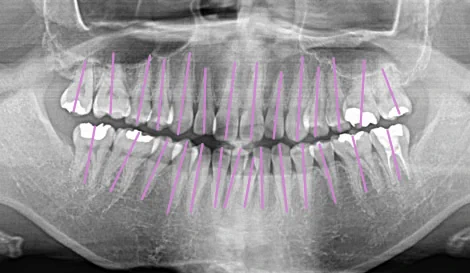

本質的な矯正は、歯茎の上に見えている部分の歯並びだけでなく、

歯茎の下の歯根がキレイに並んでこそ実現します。

このケースでは、並行に並んでいなかった歯根からしっかりと矯正を行い、

1年弱の矯正期間で、歯根まで並行にならぶキレイな歯並びとなりました。

歯根がきれいに並んでいることで、歯周病のリスクを抑え、長持ちする歯へと改善されました。